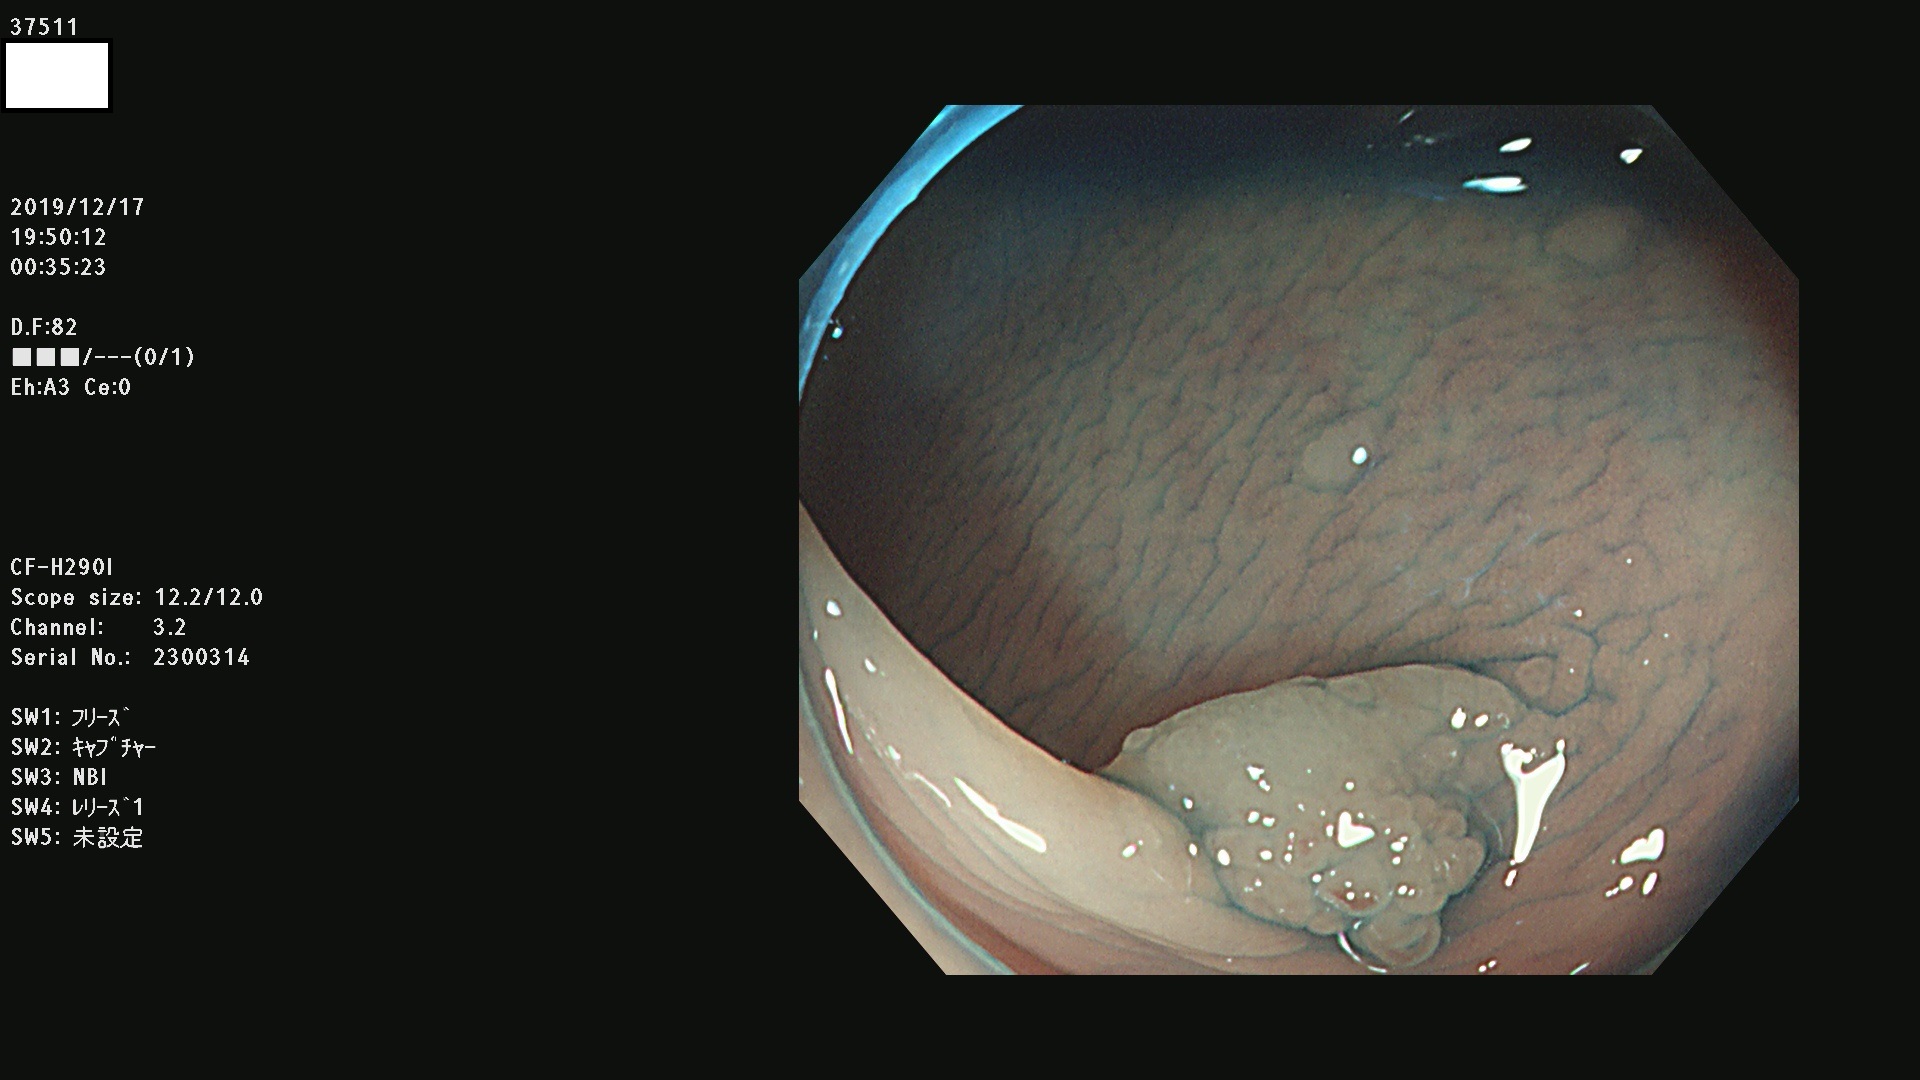

腺腫発見率 67 % (カルテ番号 37500〜37599の100名の方の検査結果で集計)大腸癌検診最新情報

以下のカルテ番号の方に腺腫(Adenoma,Group3〜5)が見つかりました(集計法)

37500 37502 37503 37505 37508 37509 37510 37511 37512 37513 37514 37517 37519 37520 37521 37525 37526(SSAPのみ) 37527 37528 37529 37531 37532 37533 37534 37536 37538(SSAPのみ) 37539 37541 37542 37543 37547 37548 37549(SSAPのみ) 37550 37552 37555 37556 37561 37562 37563(SSAPのみ) 37564 37565 37566 37567 37568 37570 37571 37572 37573 37574 37575(SSAPのみ) 37576 37577 37579 37580 37582 37583 37586(SSAPのみ) 37587 37588(SSAPのみ) 37590 37593(SSAPのみ) 37594 37596 37597(SSAPのみ) 37598 37599

発見困難で危険性の高い平坦型病変(上記100名より抽出) ![]()